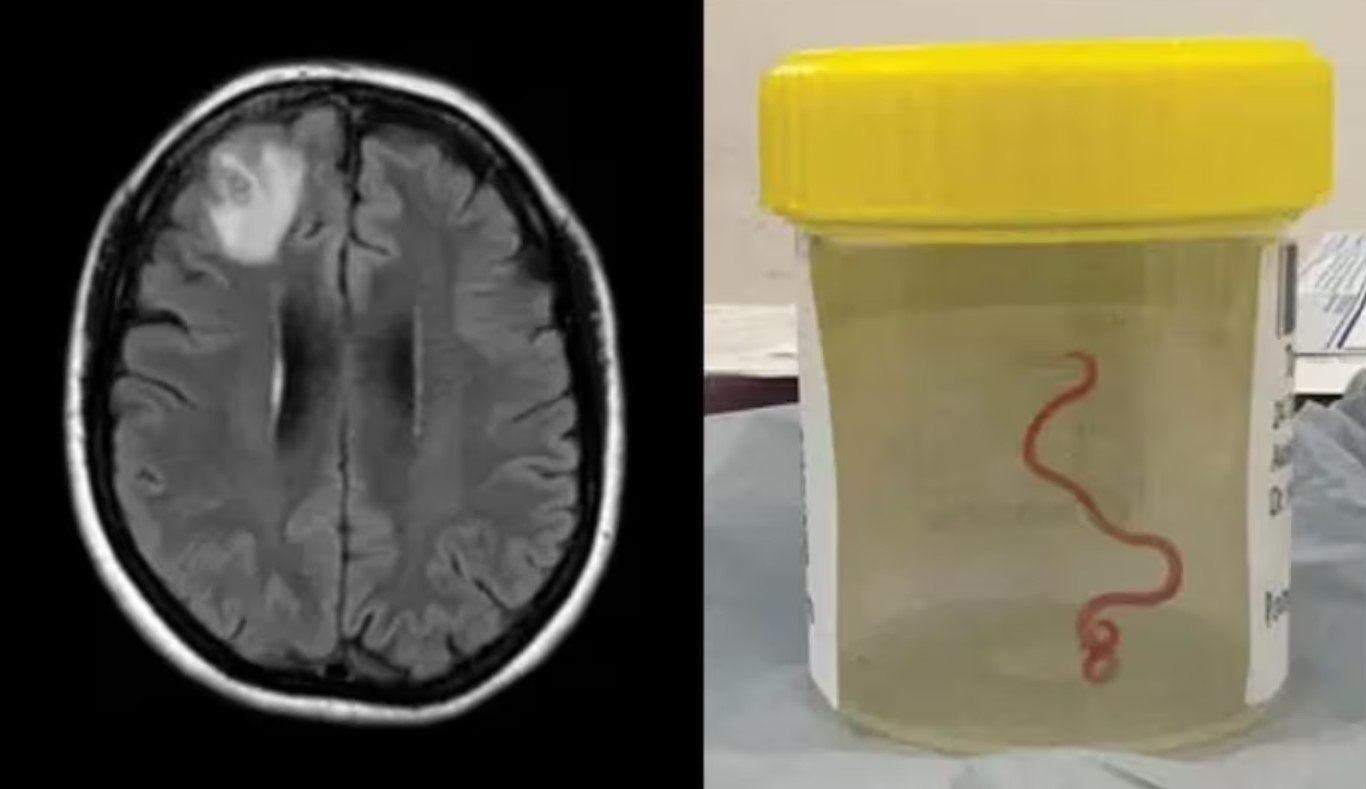

सन् २०२२ मा महिलामा डिप्रेसन र भुल्ने लक्षण पनि देखिन थालेका थिए । त्यसपछि डाक्टरहरूले उनको मस्तिष्कको एमआरआई स्क्यान गरे, जसमा केही गडबडीहरू पत्ता लाग्यो। त्यसपछि शल्यक्रिया गर्न सल्लाह दिइयो। तर पछि थाहा भयो मस्तिष्कमा जिउँदो कीरा छ ।

सर्जिकल टोलीले भेटेको तीन इन्च लामो चम्किलो रातो परजीवी राउन्डवर्म थियो जसलाई वैज्ञानिकहरूले ओफिडास्करिस रोबर्टसी भनेर चिन्छन्। महिलाको दिमागमा यो किरा घुमिरहेको थियो । यो महिलामा भेटिनु पनि अनौठो छ किनभने यो सामान्यतया सर्पमा पाइन्छ, मानिसमा होइन। यो विशेष प्रकारको राउन्डवर्म कार्पेट पाइथनमा पाइन्छ । यो सर्प अष्ट्रेलिया, इन्डोनेसिया र पपुवा न्यू गिनीमा पाइन्छ।